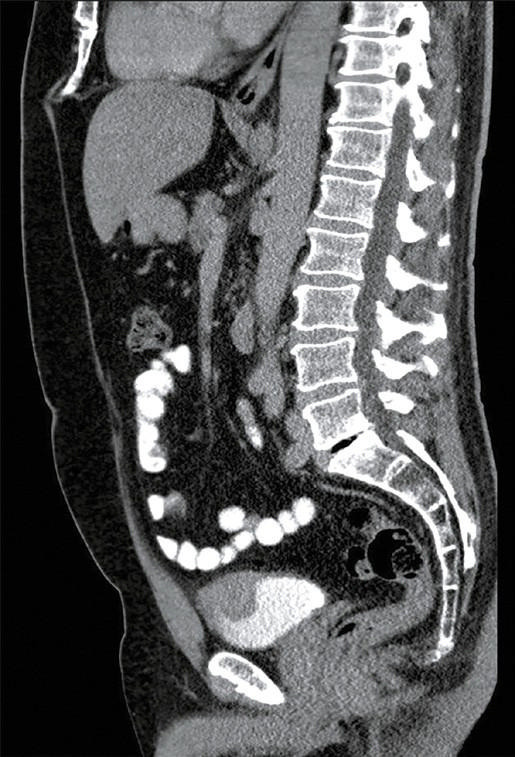

膀胱炎症性肌纤维母细胞瘤(IMTs)是罕见的,文献报道的病例数量有限。完全切除阴性切缘对于降低复发风险至关重要,同时保留膀胱功能对患者也至关重要。本研究描述了一名56岁的膀胱穹窿IMT患者,采用机器人辅助部分膀胱切除术,并辅以围手术期膀胱镜纹身来精确划定肿瘤边缘。手术首先使用黑眼染料在病变部位进行膀胱镜纹身,然后使用达芬奇Xi系统进行机器人切除。在保留膀胱容量的情况下,进行了完全的经壁切除和2层膀胱闭合。患者失血极少,术中无并发症,术后2天出院。随访检查,包括膀胱镜检查和计算机断层扫描,证实术后12个月无复发。膀胱镜纹身有助于术中肿瘤的明确定位,实现精确的切除和最小的膀胱壁损失。这种方法解决了机器人膀胱手术的一个关键挑战——在保持功能结果的同时缺乏触觉反馈。机器人辅助部分膀胱切除术与膀胱镜纹身是最大经尿道切除的一个有希望的替代方案,特别是在保留膀胱的三模治疗的背景下,对于那些不符合条件或不愿接受根治性膀胱切除术的患者。考虑到越来越多的人关注微创手术和全身治疗的进步,这项技术尤其重要。在未来,这种方法可以适用于输尿管机器人手术,以提高病灶定位。

Inflammatory myofibroblastic tumors (IMTs) of the bladder are rare, with a limited number of cases reported in the literature. Complete resection with negative margins is essential to reduce the risk of recurrence, while bladder function preservation is also crucial for the patient. This study describes a 56‑year‑old patient with a bladder dome IMT managed using robot‑assisted partial cystectomy facili‑ tated by perioperative cystoscopic tattooing to precisely demarcate the tumor margins. The procedure began with cystoscopic tattooing of the lesion using Black Eye dye, followed by robotic resection with the da Vinci Xi system. Complete transmural resection and a 2‑layer bladder closure were performed, with preservation of the bladder capacity. The patient experienced minimal blood loss, no intraopera‑ tive complications, and was discharged 2 days after the procedure. Follow‑up examinations, including cystoscopy and computed tomography, confirmed no recurrence 12 months after surgery. Cystoscopic tattooing facilitated clear intraoperative tumor localization, enabling precise resection and minimal bladder wall loss. This approach addressed a key challenge of robotic bladder surgery-lack of tactile feedback-while maintaining functional outcomes. Robot‑assisted partial cystectomy with cystoscopic tattooing represents a promising alternative to maximal transurethral resection, especially in the context of bladder‑sparing trimodal therapy, for patients who are not eligible for or unwilling to undergo radical cystectomy. This technique is particularly relevant given the increasing focus on minimally invasive procedures and advancements in systemic therapy. In the future, this method could be adapted for ureteral robotic surgeries to enhance lesion localization.